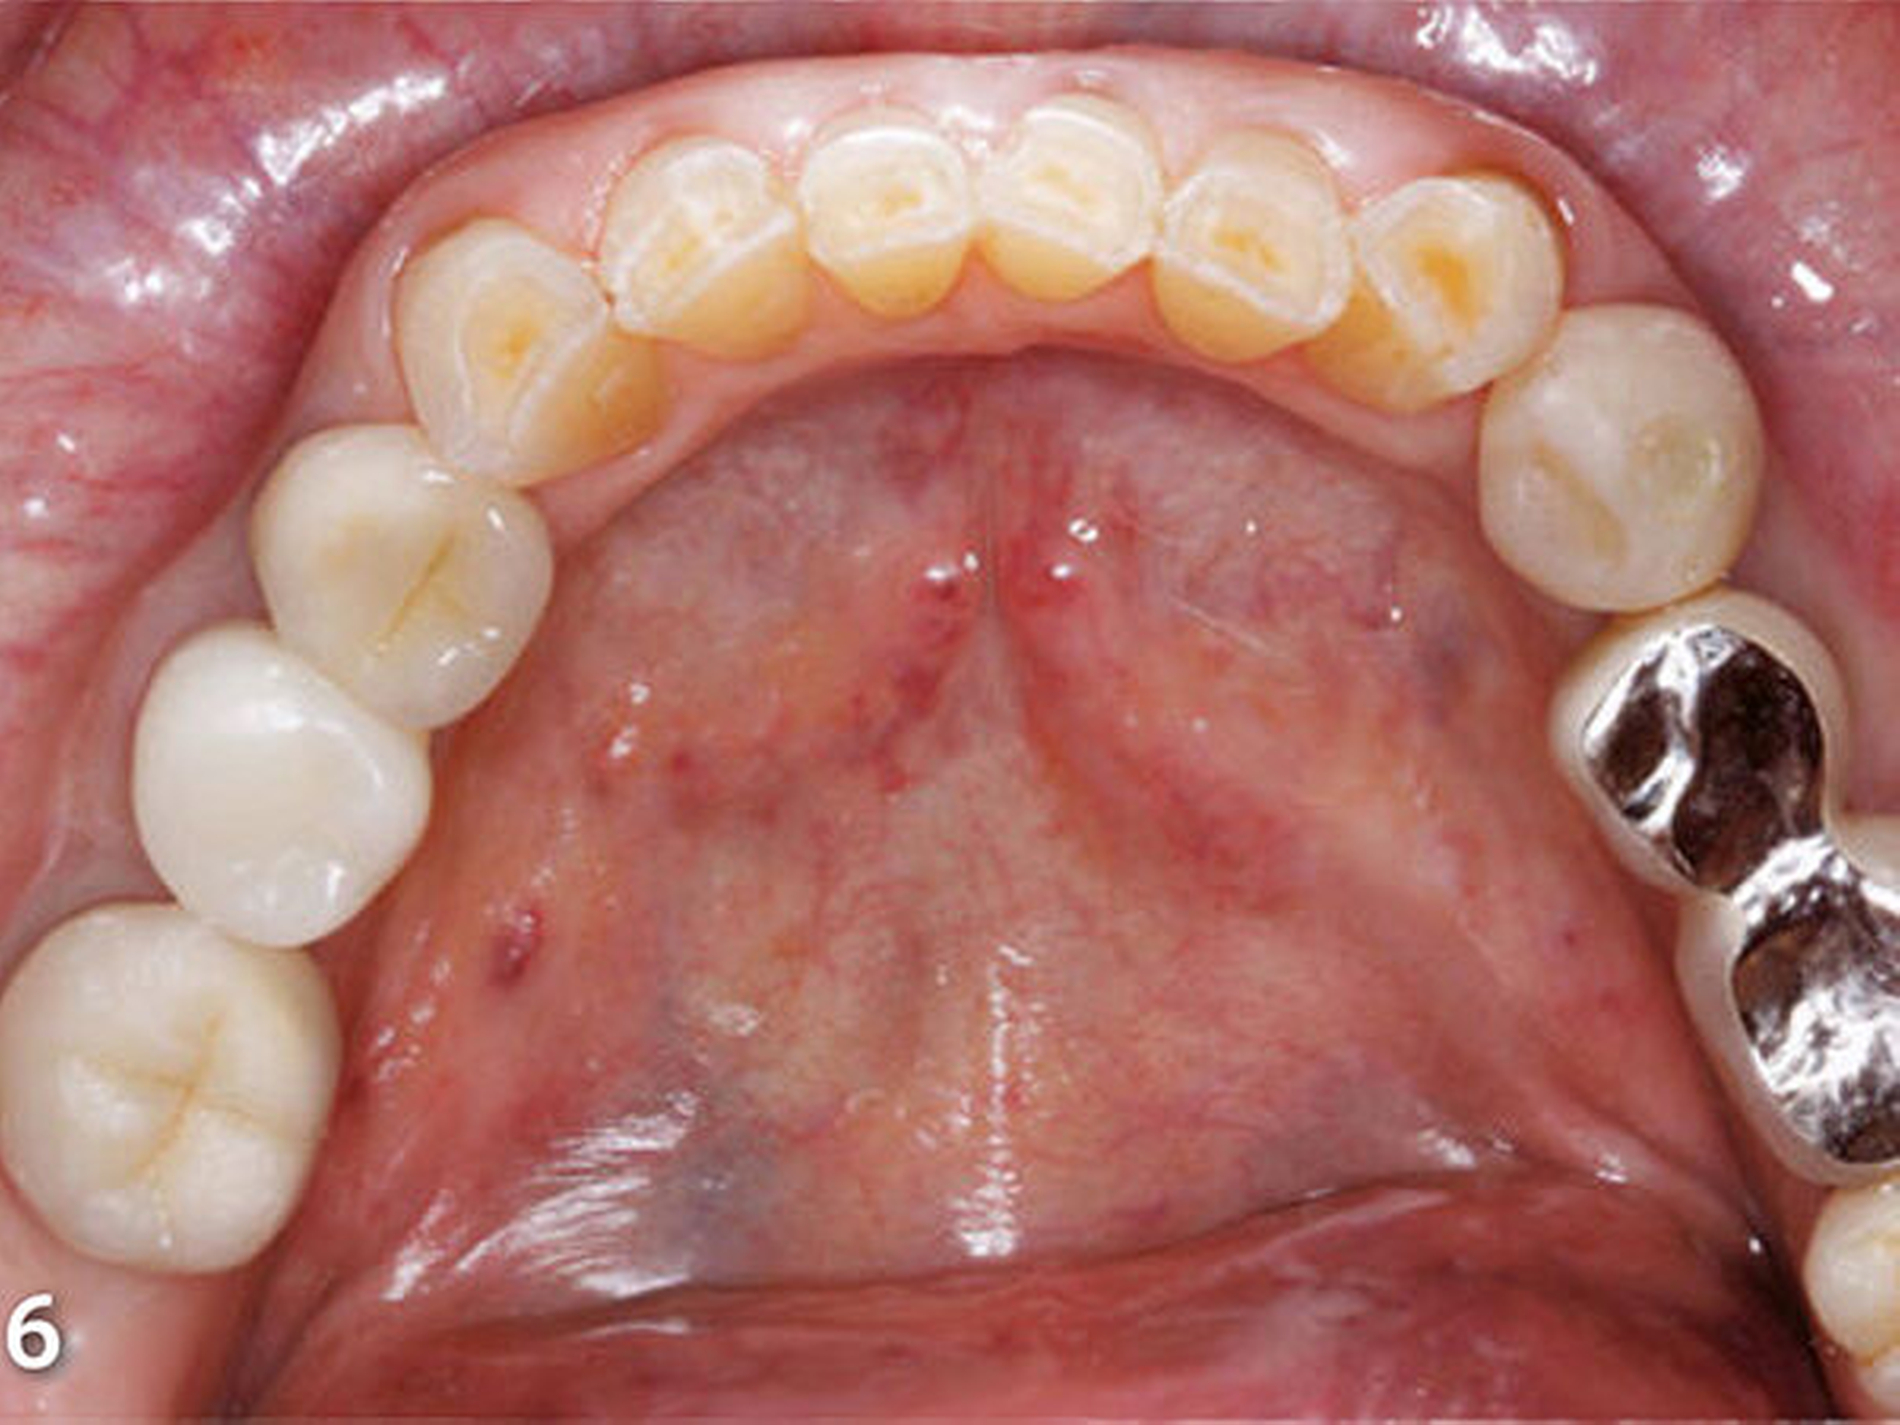

Insbesondere störten die Patientin aber der gravierende Farbunterschied der Unterkieferfront zu den Keramikverblendungen der Rekonstruktionen des Oberkiefers und die Form bzw. Größe der unteren Frontzähne (Abb.5). Darüber hinaus entsprachen die insuffizient ausgeformten Kauflächen der Restaurationen der Unterkieferseitenzähne nicht den Anforderungen an eine funktionsorientierte Gestaltung der okklusalen Anatomie (Abb.6).